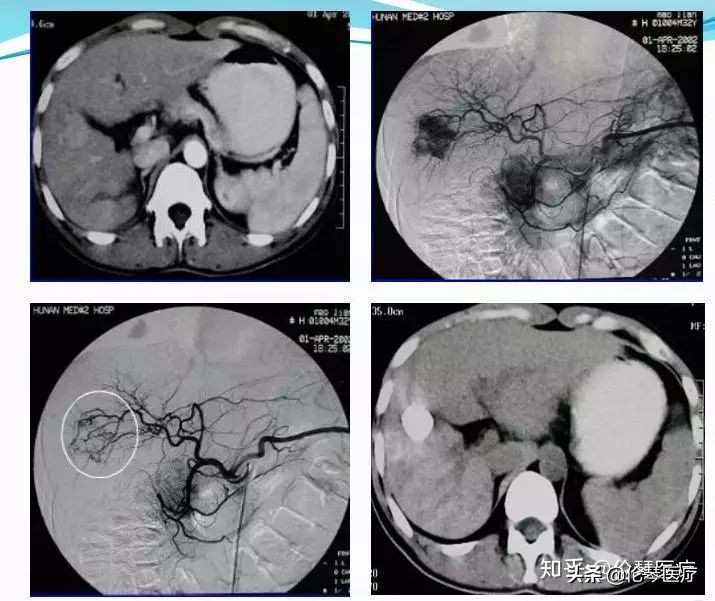

这是给大家看一个肝癌的栓塞治疗。首先,CT明确诊断,通过DSA造影看到非常明确的肿瘤染色。然后注入了栓塞剂碘油,通过碘油在肿瘤里面的沉积,就看到整个肿瘤几乎全部给栓塞剂覆盖了。

这是一个典型的血管瘤,大家看CT上有非常明显的强化。通过DSA造影可以看到三个大小不等的血管瘤,我们直接做栓塞治疗。不良反应及并发症当中,比较常见的有栓塞后综合症、胆囊炎、胆囊坏死、胰腺炎、胃十二指肠溃疡等。